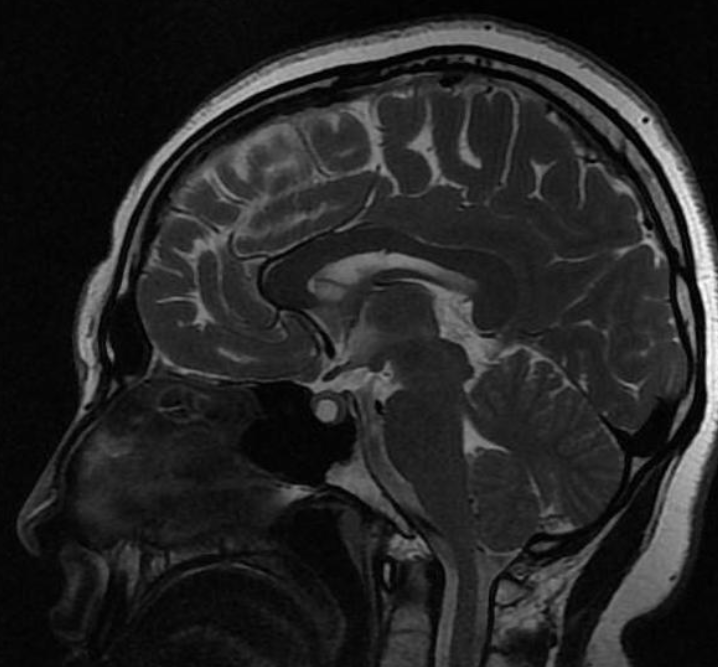

Qual é o padrão de Chiari I

A

Deslocamento caudal das tonsilas cerebelares > 6 mm (infância) Associação com Hidro-siringomielia 70%

Chiari II

Qual é o padrão de Chiari II (arnold-chiari)

Deslocamento caudal das tonsilas cerebelares, do tronco cerebral, da medula oblonga, do IV ventrículo; Associação com Mielomeningocele; Craniolacunia (lesão radioluscente na calota); Disgenesia do corpo caloso Inserção baixa da tenda do cerebelo e baixa da tórcula (contrário de dandy), Herniação superior do cerebelo (com aspecto em torre), comprimindo o mesencéfalo e causando o tectum em bico. Clivus encurtado, fossa posterior pequena (contrário de dandy), curso anatomico alterado das artérias cerebelares postero inferiores (PAICAS); Anormalidades supratentoriais: Ventriculomegalia supratentorial, angulação anterior e inferior dos cornos frontais (aparência em asa de morcego), Colpocefalia (cornos occipitais maiores que os frontais dos ventrículos laterais), fenestração da foice cerebral (hipoplasica) com interdigitação dos giros corticais;